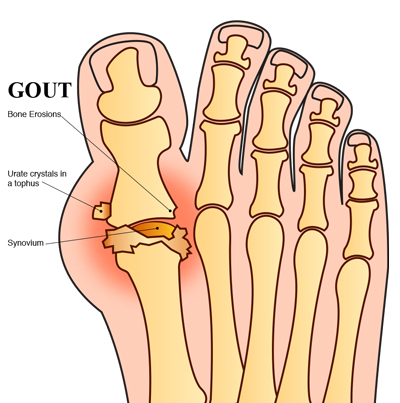

در واقع نقرس بیماری است که در اثر رسوب اسیداوریک در بافتهای بدن، مفاصل و کلیهها اتفاق میافتد. هنگامی که غلظت اسید اوریک در خون از حدی بالاتر میرود، به کریستال تبدیل میشود و رسوب میکند.

نقرس عمدتا به شکل بیماری مفصلی ظهور میکند و ابتدا خودش را با التهاب حاد یک مفصل نشان میدهد. در اکثر موارد شب هنگام حملات نقرس شروع شده و با درد شدید موجب بیخوابی فرد میشود. ظرف یکساعت این درد موجب قرمزی و التهاب مفصل میشود. این التهابات ممکن است در همه مفاصل رخ دهد، اما بیشتر از همه مفصل شصت و مچ پا و زانو را درگیر میکند.

در بعضی افراد نقرس به صورت سنگهای اسیداوریک موجود در ادرار ظاهر میشود،اگر مفاصل به ویژه مفاصل شصت و مچ پا یا زانو به طور حاد ورم کرد، یکی از تشخیصها نقرس است. در مفاصلی که قادر هستیم، مایع مفصلی را میکشیم، در زیر میکروسکوپ اگر رسوبات اسیداوریک ملاحظه شود، فرد مبتلا به نقرس است. این کار را خصوصا درباره زانو انجام میدهیم؛ چراکه با عفونت اشتباه گرفته میشود.